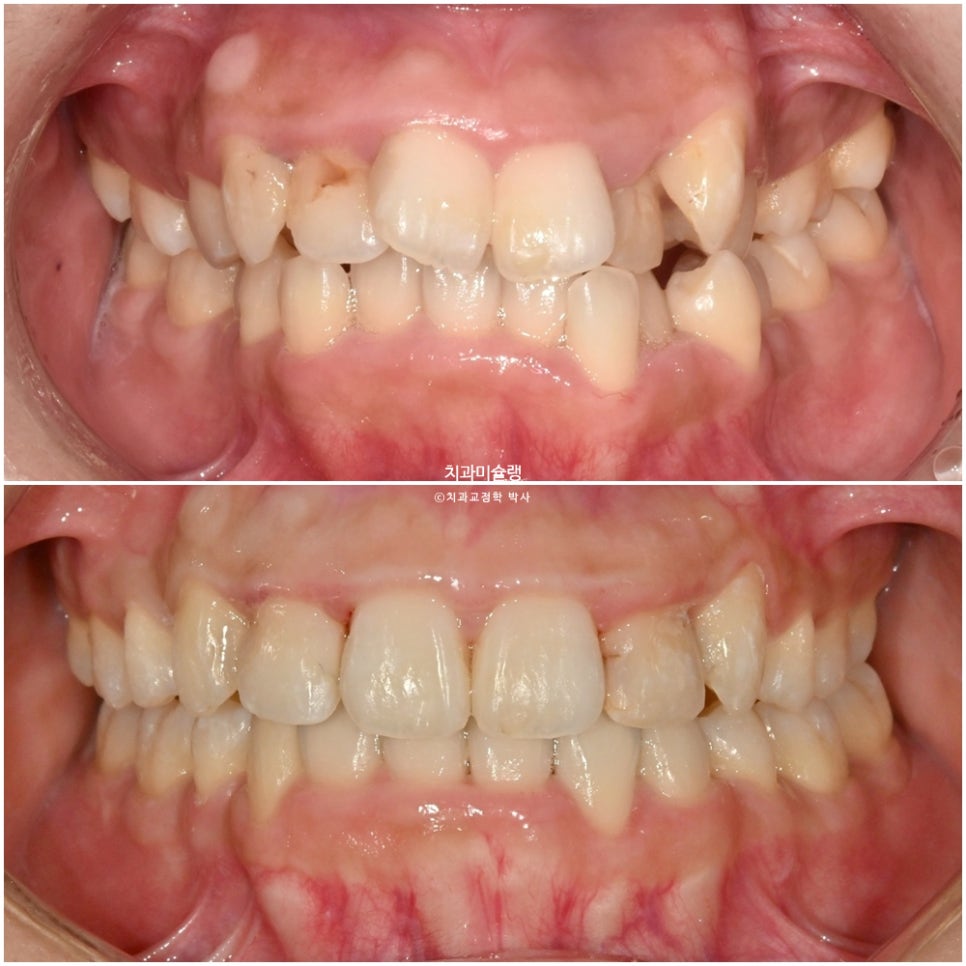

닷니와 반대교합이 보입니다.

앞니에 갈색 부분은 예전에 레진으로 충치치료한 부분이 변색된 것입니다.

작은어금니 쪽에는 반대교합도 보입니다.

악궁이 소구치 부위가 안으로 쓰러져 찌그러진 모양입니다.

총생 (치아 삐뚤한 정도) 가 심하고 돌출감도 있어 작은어금니 4개 발치가 불가피한 상황입니다.

중심선은 잘 맞으며 송곳니 덧니는 예쁘게 배열되었습니다.

잇몸이 치아를 과하게 많이 덮고 있는 만큼 블랙트라이앵글 없이 마무리 되었습니다.

치료 전후 비교 결과

이제 전후비교 보겠습니다.

총 치료기간은 2년 4개월, 재제작은 1회 했습니다.

아래앞니 보이는양이 적어 과개교합인것 처럼 보이지만, 윗니가 아랫니를 덮는 양은 2mm로 정상이며 아래앞니 잇몸이 치아를 많이 덮고 있기 때문에 마치 과개교합처럼 보입니다.

아랫니 뿐만 아니라 윗니도 잇몸이 치아를 과하게 많이 덮는 형태라 교정 후 치아의 가로 세로 4:5 비율을 회복하기 위한 잇몸성형을 권했지만 환자분이 원치않아 하지 않았습니다.

심미적으로 아쉬운 부분입니다.

2023.08-2026.02

어금니 교합은 물샐틈없이 좋습니다.

아랫입술과 평행한 원호를 그리는 이상적인 스마일라인

뻗치지도 옥니도 아닌 적절한 앞니 각도

돌출이 해소되며 입이 자연스럽게 다물리게 되었습니다.